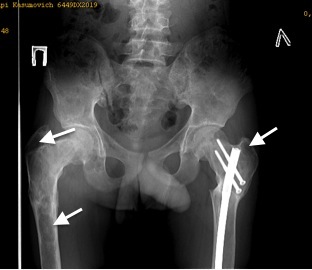

На рис. 8 — рентгенограмма костей таза в возрасте 17 лет: очаги ФД в правой бедренной кости. Остеосинтез левой бедренной кости.

Рис. 8. Очаги фиброзной дисплазии в правой бедренной кости. Остеосинтез левой бедренной кости